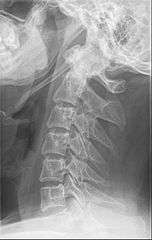

Anteroposterior and lateral radiographs of cervical spine showing ossification of the stylohyoid ligament on both sides

Imaging is important and is diagnostic. Visualizing the styloid process on a CT scan with 3D reconstruction is the suggested imaging technique.[6] The enlarged styloid may be visible on an orthopantogram or a lateral soft tissue X ray of the neck.